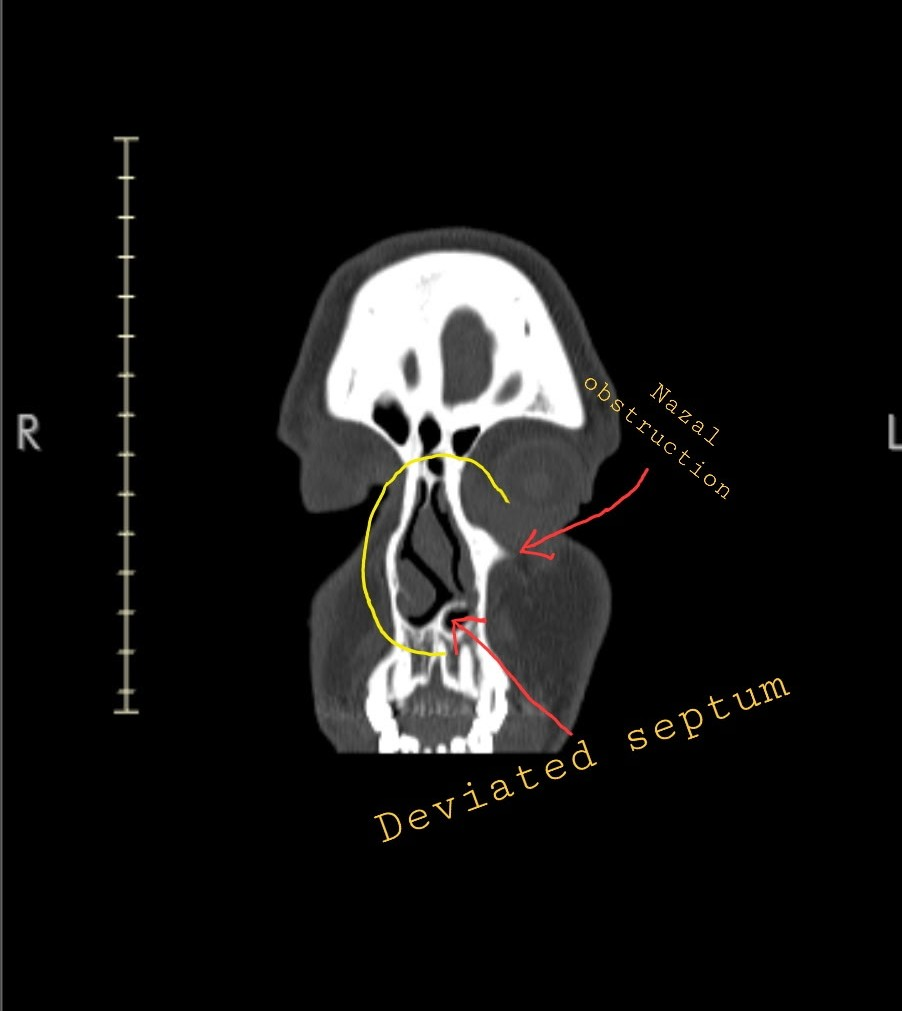

Now at 25, I’m facing the long-term effects: a broken nose, a completely deviated septum, and collapsed sinuses that make it hard to breathe, sleep, or live comfortably day to day.

Correcting the severe septal deviation

Making internal changes to restore healthy airflow and sinus function